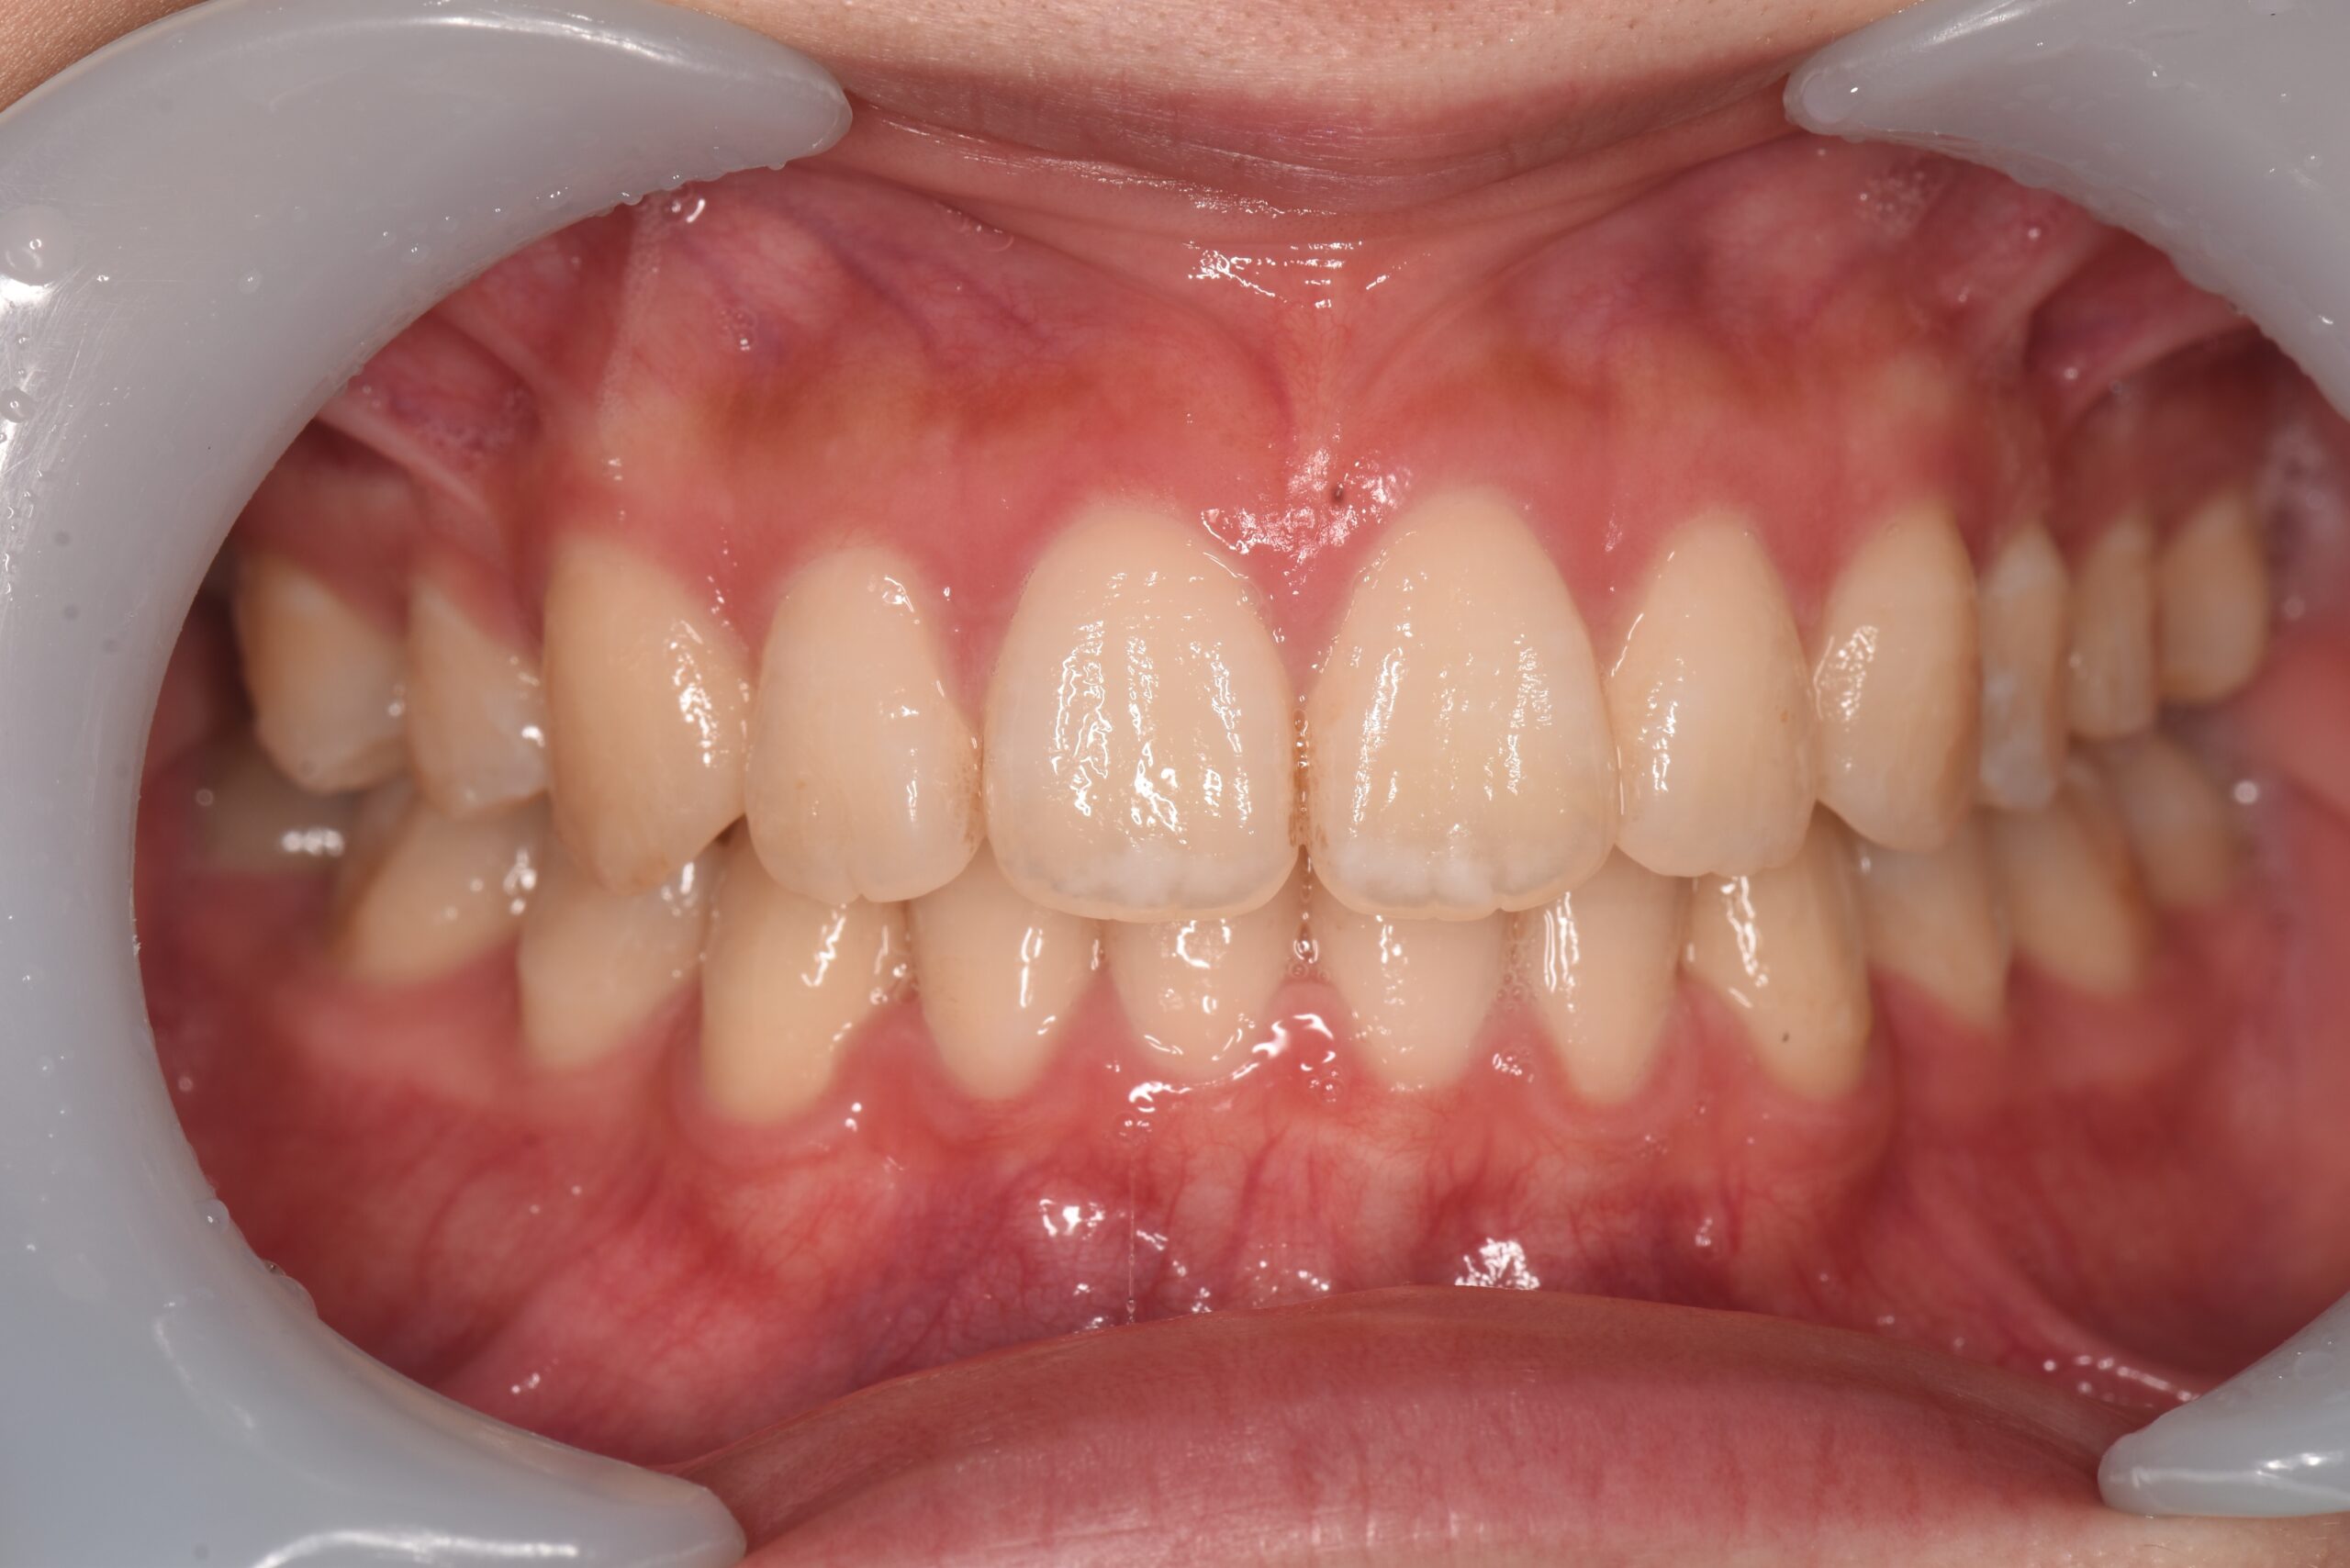

犬歯が外側に飛び出して、他の歯に重なっている状態です。八重歯は噛み合わせに問題が生じたり、歯磨きがしにくいことでむし歯や歯周病の原因となることがあります。